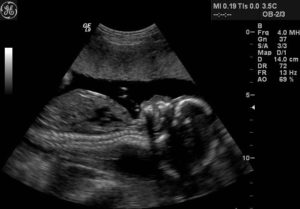

УЗИ на этом сроке фиксирует уменьшение движений плода, что является нормальным из-за его большого размера. Во время УЗИ выполняется фетометрия, или подсчет основных параметров малыша и сравнение с нормой – сколько он должен весить, какой иметь рост и т.д. Основные показатели для ребенка в 37 недель таковы:

1. Бипариетальный размер головы – около 90 мм.

2. Голова по окружности – около 325 мм.

3. Размер лобно-затылочный – 106-126 мм.

4. Диаметр грудной клетки – 93-94 мм.

5. Окружность живота – 300-361 мм.

6. Кость бедра (длина) – 66-76 мм.

7. Кость голени – 59-67 мм.

8. Кость плеча – 59-69 мм.

9. Кость предплечья – 59-67 мм.

Исходя из указанных цифр, малыш к 37 неделе выглядит совсем как новорожденный, поэтому вскоре он появится на свет. По УЗИ на этом сроке врач сделает все выводы о предстоящих родах и способе родоразрешения, а при наличии отклонений в здоровье матери и ребенка – порекомендует процедуры и лечение для их устранения.